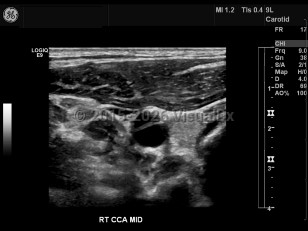

Carotid artery dissection

Carotid artery dissection is tearing of the carotid artery wall between the intimal and medial layers, resulting in an abnormal collection of blood or intramural hematoma. May compromise the arterial blood flow, causing ischemic stroke. Painful condition. Characteristic findings include headache and/or neck pain on the side of the dissection, periorbital headache / pain, miosis, ptosis, amaurosis fugax, tinnitus, facial numbness, dysgeusia, tongue paresis, and syncope. Caused by a weakness in the arterial wall. Sometimes the result of blunt trauma to the neck or head as a result of a sports injury, strenuous exercise, whiplash, childbirth, or sexual intercourse. Certain conditions may compromise the strength of the arterial wall, including Marfan syndrome, fibromuscular dysplasia, atherosclerosis, Ehlers-Danlos syndrome type 4, and homocystinuria.

Carotid artery dissection